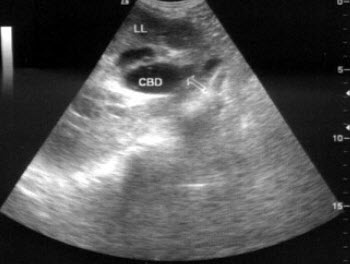

A.①

患者女48岁,上腹部疼痛不适3个月,皮肤巩膜黄染1个月余。B超检查如图所示,根据超声声像图诊断为()

A.胆总管下段癌

B.壶腹部癌

C.胰头癌

D.腹主动脉旁肿大淋巴结

E.结肠癌